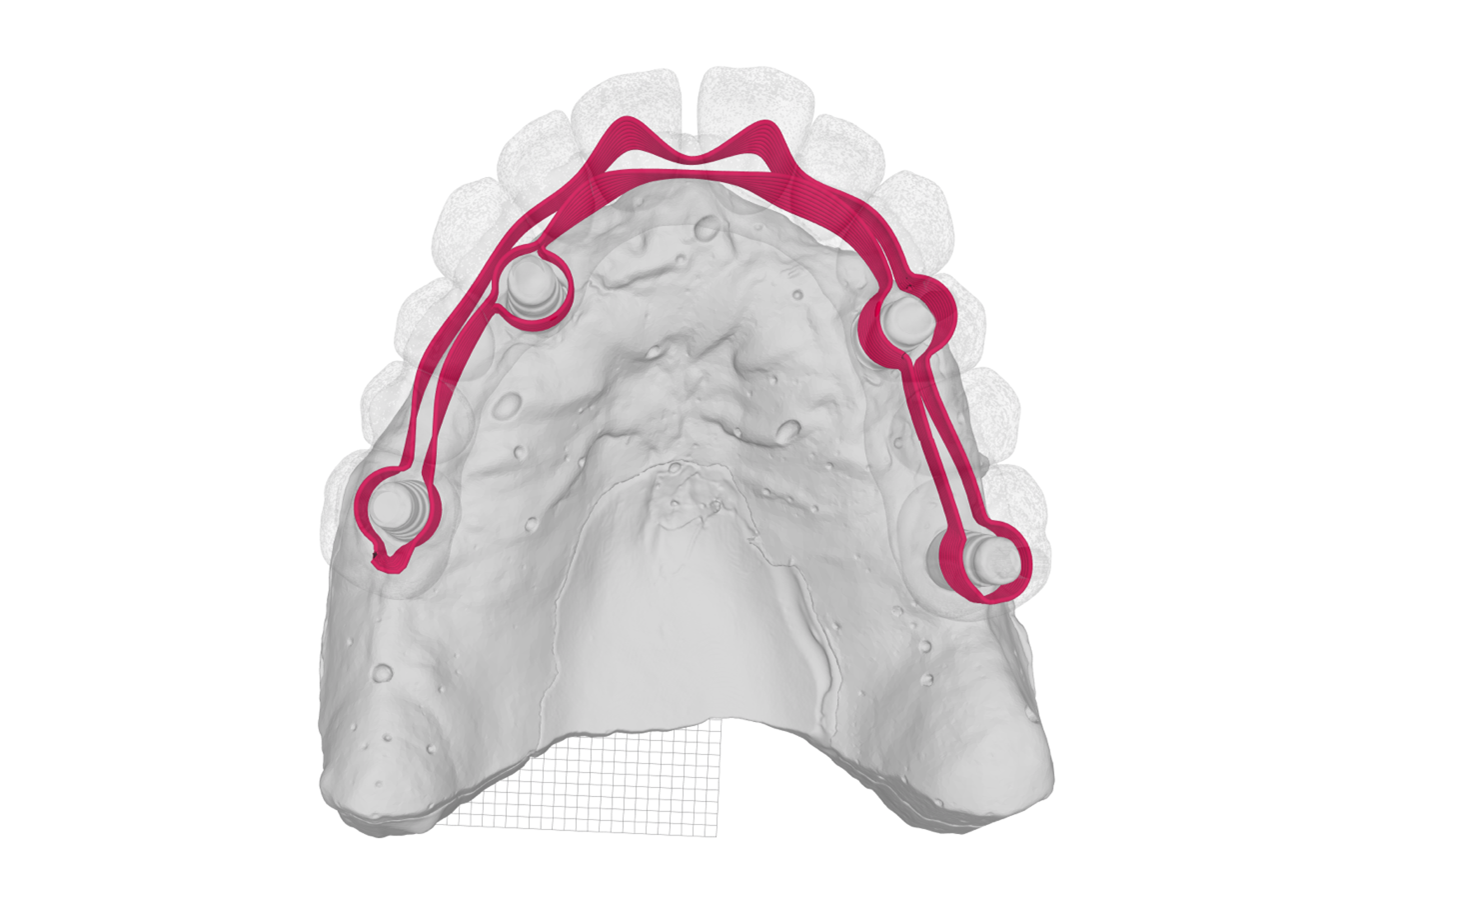

Fig. 15 Barra di rinforzo progettata dal software di Hi-Fiber

Fig. 16 Visualizzazione digitale della barra Hi-Fiber

per realizzare il caso con il protocollo di lavoro di Artitec S.n.c., che non

prevede l’utilizzo di denti del commercio.